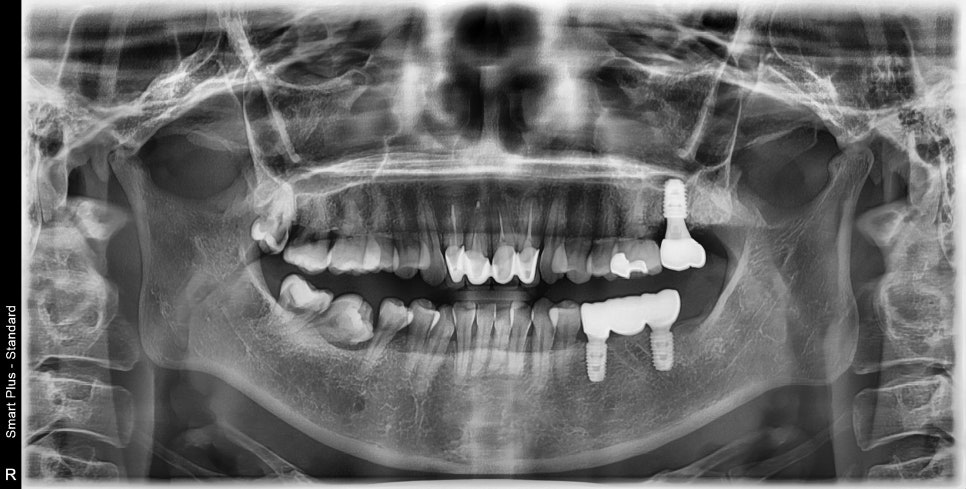

왼쪽 치아 발치 후 임플란트 수술 후 보철까지 완성되었습니다.

다행히 오른쪽은 쓰러져있는 어금니들이 위 어금니를 받쳐주고 있어 교합의 변화가 크지 않아 기존 충치치료만 진행하고, 아래 부위만 임플란트 수술이 진행되었습니다.

치아가 쓰러져있는 공간이 매우 컸기 때문에 임플란트 주변의 빈 공간에 치조골 이식술을 동반하여

임플란트 주변에 뼈를 보강해 주는 작업까지 진행되었습니다.

수술을 나눠서 하고 오른쪽은 왼쪽에 비해 수술 기간이 길어져서 총 치료 기간이 길어질 수밖에 없었지만 환자분께서 잘 따라와 주셔서 잘 마칠 수 있었던 것 같습니다.